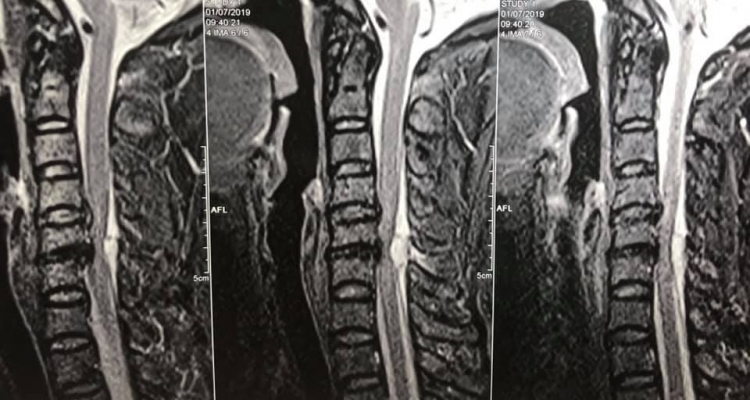

Bà Hồng được gia đình đưa lên bệnh viện Hà Nam cấp cứu rồi chuyển thẳng lên bệnh viện Việt Đức. Tại đây, các bác sĩ đã chỉ định cho bà đi chụp cộng hưởng từ để tìm kiếm nguyên nhân. Phim chụp cho thấy bà Hồng có một khối máu tụ rất to đang chèn ép nặng cột sống cổ. Đó chính là nguyên nhân gây mất cảm giác và khả năng vận động của bà.

| Hình ảnh khối máu tụ chèn ép tủy sống trên phim chụp cộng hưởng từ. Ảnh: BS Quốc Khánh |